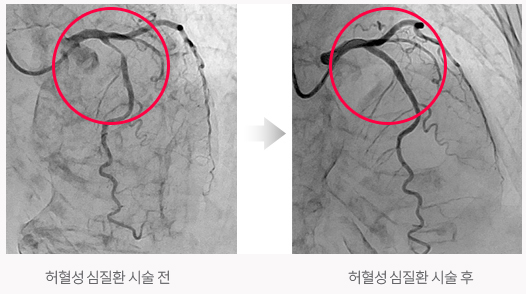

허혈성 심질환

관상동맥이 죽상경화증으로 협착되거나 혈관수축으로 인해 심장 근육에 충분한 양만큼의 혈액을 공급해주지 못해서 생기는 질환으로 협심증, 심근경색증 등이 있습니다.

허혈성 심질환의 치료

관상동맥 중재술

관상동맥 협착 병변을 치료하는 재개통술의 하나로 풍선을 이용하여 좁아진 관상동맥을 넓히는 풍선확장술, 풍선확장술 후 혈관폐쇄를 방지하고 관상동맥 내경의 확장을 유지하기 위한 스텐트 삽입술 등을 시행합니다.